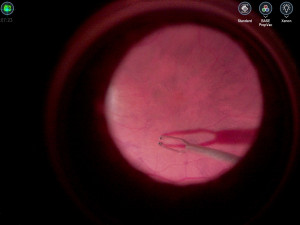

Při operacích sítnice, sklivce a také při odstranění šedého zákalu pomůže lékařům z oční kliniky Fakultní nemocnice Olomouc nový operační systém. Usnadní jemnou a precizní práci v nitru lidského oka. Aparatura má plochou 3D obrazovku s vysokým rozlišením, kamery, počítače a speciální konzole.

Nejmodernější verze operačního systému podle primáře oční kliniky Michala Hrevuše očním chirurgům přinesla dříve netušené zobrazovací možnosti, jelikož 3D kamera je napojena na operační mikroskop a obraz je přenášen na velký LCD panel.

"Díky většímu zobrazení operačního pole mám lepší přehled o tom, co se v oku děje," uvedl Hrevuš, podle kterého operatér svůj výkon kontroluje na velké obrazovce. Nový zobrazovací systém zatím oční lékaři využili již při dvou desítkách operací. "Jeho vytížení bude intenzivnější, budeme jej využívat na všechny nitrooční operace, kterých provádíme přes 2000 ročně," dodal Hrevuš.

"Digitalizovaný obraz je větší a lze s ním dále pracovat. Kromě samotného operačního pole má lékař na monitoru k dispozici také více důležitých údajů o stavu pacienta. Obraz může různě upravit, například použít barevný filtr, jímž zvýrazní vybrané oční struktury a vrstvy tkáně. Zvyšuje se tak chirurgický komfort a zlepšuje se vizualizace operované části oka," uvedl Zdeněk Plešek ze společnosti Alcon.

Nový operační systém se podle Pleška hodí i pro výuku budoucích lékařů. "Medici díky monitoru sledují v reálném čase všechny úkony operatéra a vzhledem k tomu, že operace je možné nahrávat, ať již ve formátu videa nebo fotografií, lékaři mohou záznam využít v prezentacích pro studenty nebo kolegy na odborných setkáních," dodal Plešek.